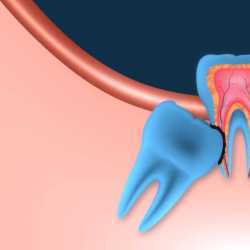

Inicio Especialidades Cirurgia